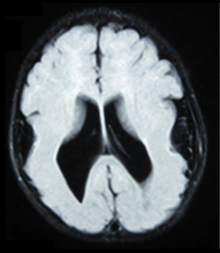

There are different tests or methods used to determine GPR56 expression or visuals of the brain to analyze the specific sections that are affected. These tests for example, using animals such as mice, RNAi, Behavioral assay, Electron microscopy, CT scan, or MRI demonstrate different results that concludes an affected BFPP patient.[13] MRI's reveal either irregularity to the cortical surface suggestive of multiple small folds or an irregular, scalloped appearance of the gray matter-white matter junction.

Neuroimaging The diagnosis of polymicrogyria is typically made by magnetic resonance imaging (MRI) since computed tomography (CT) and other imaging methods generally do not have high enough resolution or adequate contrast to identify the small folds that define the condition. The cerebral cortex often appears abnormally thick as well because the multiple small gyri are fused, infolded, and superimposed in appearance.[11]

- Radiological findings (MRI) demonstrated symmetric generalized polymicrogyria with decreasing anterior-posterior gradient, most prominent in frontoparietal cortex.[11]